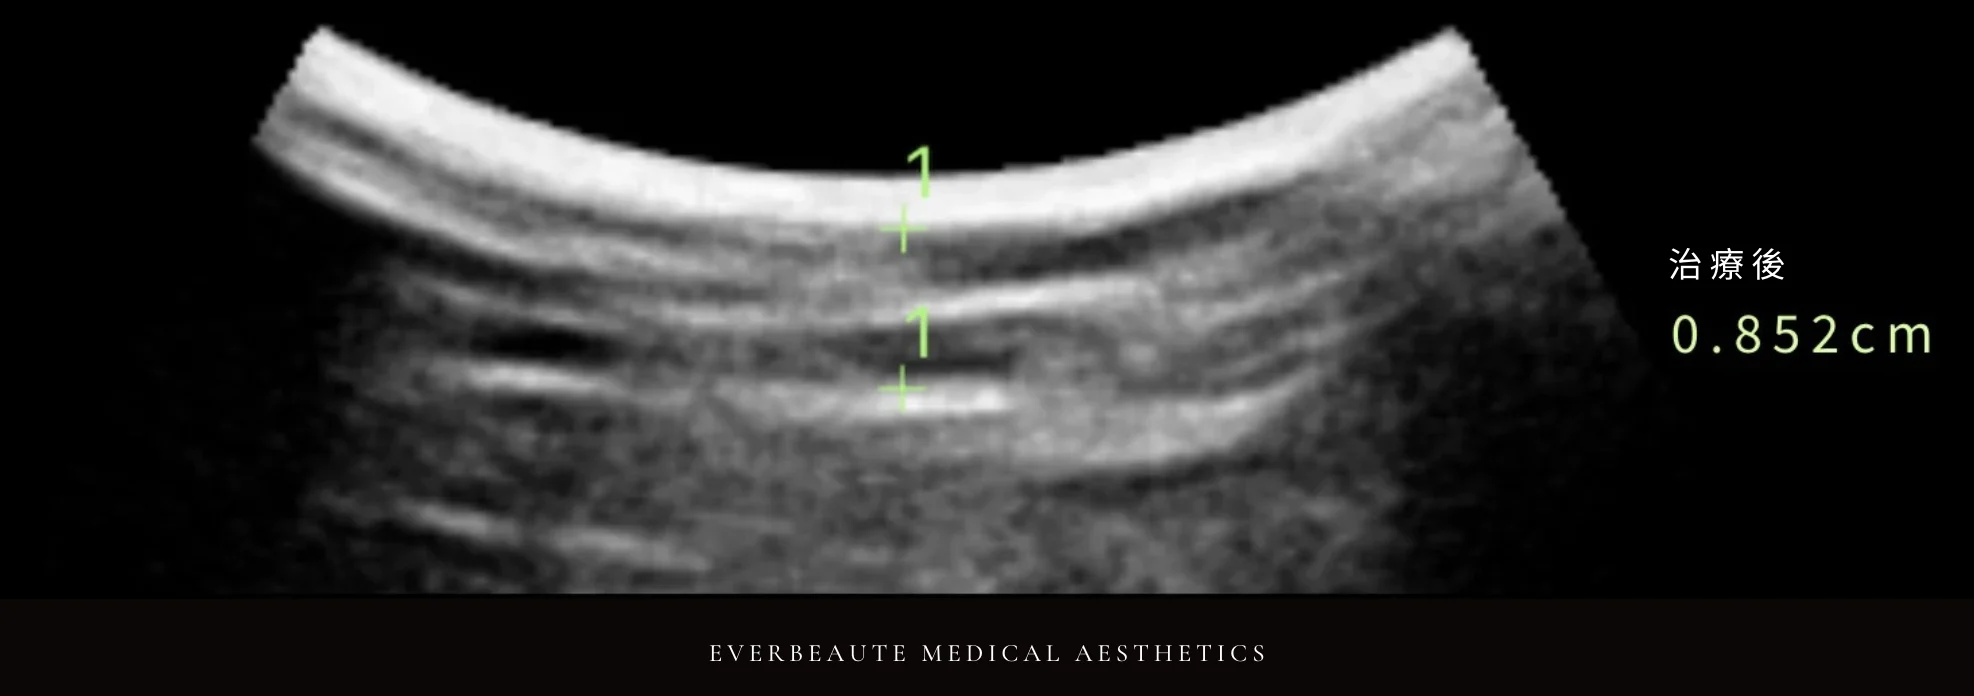

經術前與術後超音波檢查比較,上臂脂肪厚度由1.162公分減少至0.852公分,顯示脂肪厚度下降約26.7%,呈現顯著改善。